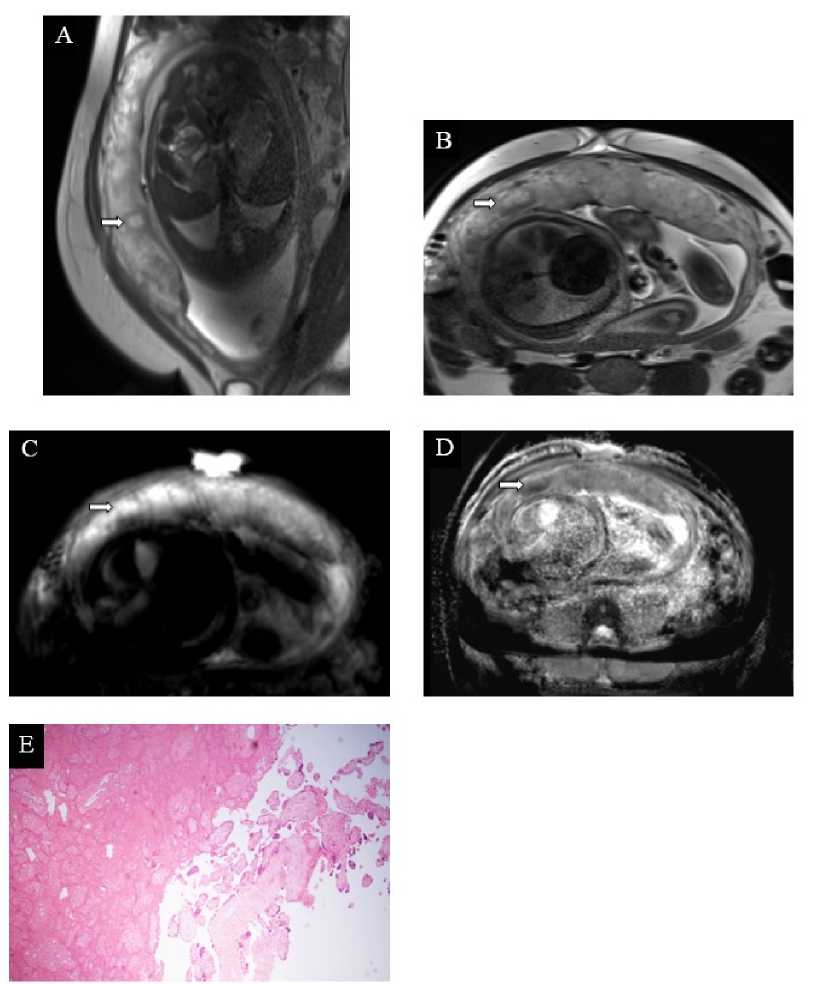

Хотя возникновение инфарктов является нормальным этапом «старения» плаценты в III триместре, увеличение числа ишемических изменений в ней с тенденцией к центральному расположению в I и II триместрах при гипертензивных расстройствах можно считать одним из характерных признаков. Инфаркты возникают за счёт тромботической окклюзии артериол материнской части плаценты на фоне децидуальной артериопатии, что приводит к ишемическому некрозу ворсин и коллапсу межворсинчатого пространства (рис. 4, Д) [17, 22]. В нашем исследовании инфаркты плаценты отмечались в 69% случаев (9 наблюдений из 13).

Рисунок 4. Инфаркт плаценты. А–D. МРТ плаценты на 37 н.г., Т2-ВИ (А и Б), ДВИ (В) и карты ИКД (Г), сагиттальная плоскость (А), аксиальная плоскость (Б-Г), диагноз – умеренная преэклампсия (пациентка № 5). В центральных отделах плаценты субхориально определяется инфаркт (стрелки), представленный отграниченным округлым участком гиперинтенсивного МР-сигнала на Т2-ВИ, окружённым гипоинтенсивным ободком, характеризующимся истинным ограничением МР-диффузии по данным ДВИ и карт ИКД. Е. Плацента при тяжёлой преэклампсии, 26 н.г., световая микроскопия х50, окраска гематоксилин-эозин (пациентка № 11). Инфаркт плаценты в хронической стадии

Figure 4 . Placental infarction. A–D. Placental MRI at 37 weeks of gestation, T2-WI (A and B), DWI (C) and ADC maps (D), sagittal plane (A), axial plane (B-D), diagnosis – moderate preeclampsia (patient 5). A subchorionic placental infarction is visualized in the central regions of the placenta (arrows), appearing as a well-defined, rounded hyperintense area on T2-WI, surrounded by a hypointense rim, consistent with true diffusion restriction on DWI and ADC maps. E. Placenta in severe preeclampsia, 26 weeks of gestation, x50 light microscopy, hematoxylin-eosin staining (patient 11). Chronic-stage placental infarction is observed

МР-семиотика инфарктов вариабельна, поскольку происходит последовательное их развитие от острейшей стадии к хронической, сопровождающееся отложением фибрина, солей кальция и пр., и, как следствие, сменой сигнальных характеристик. Присоединение геморрагического компонента также влияет на МР-сигнал, в результате чего зона ишемии может приобретать слабогипер- или гипертинтенсивный МР-сигнал на Т1-ВИ [24].

В связи с этим в научной литературе можно встретить различные подходы к описанию инфарктов по данным МРТ. Так, Oppenheimer D. и соавт. определяют инфаркты плаценты как участки гипо-интенсивного МР-сигнала на Т2-ВИ [22], другие же отмечают, что инфаркты будут иметь «классический» вид – гиперинтенсивный сигнал на Т2-ВИ и ДВИ, гипоинтенсивный – на картах измеряемого коэффициента диффузии – ИКД [24, 25].

В настоящем исследовании инфаркты плаценты мы определяли как округлой или неправильной формы участки нарушения архитектоники плаценты, отличные от её нормального дольчатого строения, визуализируемые в трёх плоскостях, характеризующиеся очаговым повышением интенсивности МР-сигнала на Т2-ВИ и ДВИ, в ряде случаев – сопровождающиеся снижением МР-сигнала на картах ИКД, при наличии геморрагического компонента – гиперинтенсивным МР-сигналом на Т1-ВИ (рис. 4, А–Г). Ещё одной формой нарушения кровообращения в ткани плаценты, свойственной гипертензивным расстройствам, является возникновение участков кровоизлияний в виде гематом [17, 25]. Как и инфаркты, гематомы могут возникать при нормально протекающей беременности, однако чаще это происходит на ранних сроках, причём большая часть из них подвергается спонтанному регрессу ко II триместру [26, 27]. Частота возникновения гематом широко варьирует – от 0,46% до 39,5% в зависимости от срока гестации, критериев диагностики, характеристик выборки и т.д. [28]. Мы отмечали наличие данной формы нарушения внут-риплацентарного кровообращения в 5 (38%) случаях из 13 (рис. 5). МР-семиотика гематом, как и инфарктов, зависит от давности их возникновения и, в частности, от типа присутствующего в них гемоглобина и значимо не отличается от гематом других локализаций [24, 25].

Рисунок 5. Гематома плаценты. А и B. МРТ плаценты на 26 н.г., Т2-ВИ (А) и Т1-ВИ (Б), сагиттальная плоскость, диагноз – тяжёлая преэклампсия (пациентка № 11). Субхориально определяется гематома в поздней подострой стадии (стрелка). C . Плацента при тяжёлой преэклампсии, 30 н.г., световая микроскопия х50, окраска гематоксилин-эозин (пациентка № 12). Межворсинчатая гематома плаценты

Figure 5. Placental hematoma. A and B. Placental MRI at 26 weeks of gestation, T2-WI (A) and T1-WI (B), sagittal plane, diagnosis – severe preeclampsia (patient 11). A subchorionic hematoma in the late subacute stage is observed (arrow). C. Placenta in severe preeclampsia, 30 weeks of gestation, x50 light microscopy, hematoxylin-eosin staining (patient 12). Intervillous hematoma of the placenta is observe